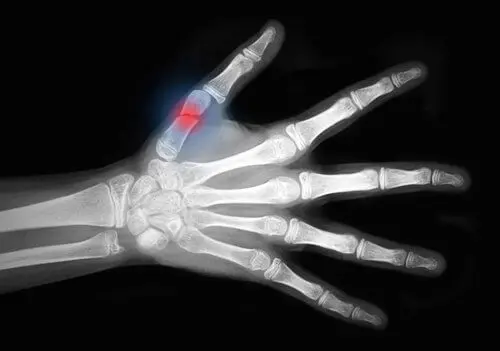

El cuerpo tiene la capacidad de regenerar el tejido óseo naturalmente, aunque a veces es un proceso lento. La curación de una fractura de hueso, tanto si es parcial como si es total, es un proceso complejo cuya velocidad y éxito dependerá de cada individuo.

De acuerdo con el contenido publicado en la plataforma Elsevier, el proceso de curación de las fracturas inicia de forma inmediata, por lo que a las dos semanas el hueso está unido por una red de fibrina. No obstante, la consolidación completa puede tomar hasta más de 6 meses en los casos más severos. Por fortuna, existen diversas técnicas que permiten acelerar este proceso.

Se trata de un proceso dinámico, constante y paulatino por el que pasan todos los huesos fracturados conocido como consolidación. La consolidación ósea cuenta con múltiples fases que pueden tardar varias semanas en completarse. En este sentido, las principales fases de la consolidación son las siguientes:

- Impacto e inducción: el impacto es el proceso que causa la ruptura del hueso, mientras que la inducción es la respuesta primaria del organismo a tal evento. Durante el proceso de inflamación inicia la migración de las células a la zona de lesión y se forma el hematoma fractuario, el cual servirá como base para la formación de nuevo hueso.

- Inflamación: luego de la inducción inicia la inflamación, en la cual llegan las células del sistema inmunitario con la finalidad de eliminar las células muertas. Esta fase prepara la zona fracturada para la síntesis de hueso e inicia la proliferación de nuevos vasos sanguíneos.

- Formación de callo blando: en esta etapa se forma una especie de tejido blando entre ambos extremos de los huesos. Este callo blando cuenta con una gran cantidad de vasos sanguíneos y se transformará en hueso sólido en las siguientes fases.

- Formación de callo duro: básicamente es el depósito de cristales de hidroxiapatita en el callo blando con la finalidad de formar tejido sólido. Se trata de una de las fases más largas de la consolidación, por lo que puede durar hasta varios meses.

- Remodelación: es la fase final del proceso de consolidación, en la que el hueso recién formado adquiere las características propias del tejido, regresando a su forma original.